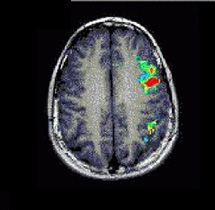

Caso 4

Paciente Paciente de sexo masculino de 9 años de edad  con una lesión neoplásica en la fisura silviana izquierda.  Sin déficit del lenguaje

Paradigma Tarea de fluidez verbal

ACTIVADO: Pensar en acciones relacionadas con los sustantivos dados

DESACTIVADO: No pensar en nada

Resultados Predominio obvio del lenguaje del lado izquierdo.  El área de Broca está bien definida junto con la circunvolución frontal superior izquierda.  Se ha descrito la asociación de la activación del cerebelo derecho con las tareas relacionadas con el lenguaje expresivo.